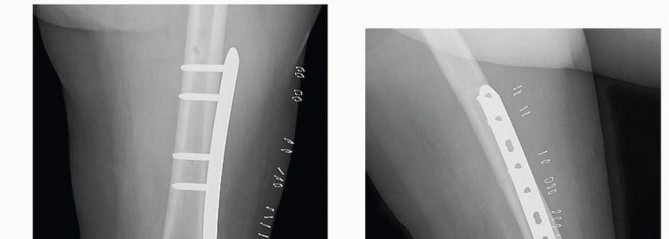

### FIG 9 • Critically ill elderly polytrauma Jehovah's witness patient with left C1 distal femur fracture. A,B. Initial injury AP and lateral views. C,D. Due to extremely low hematocrit, external fixation was the only surgical option allowed to minimize blood loss. Radiographs in bridging external fixation. The AP shows excellent alignment but the lateral shows the expected extension deformity secondary to pull of gastrocsoleus complex. E,F. After 5 weeks in an external fixator, AP and lateral radiographs show callus formation (red arrows). Patient is now cleared for definitive surgical intervention. Antegrade intramedullary nailing has been described and can be used for distal fractures with a large enough distal segment to allow for two locking screws. Malalignment has been a problem, as has adequate fixation. 4, 8 Retrograde intramedullary nailing can be used in the following cases ( FIG 10): All extra-articular type A fractures greater than 4 cm from the joint. This minimal length of the distal femur allows for multiplanar interlocking in the distal fragment. Type C1 or C2 fractures where the articular fracture can be anatomically reduced closed or with limited exposure. Percutaneous screws are used for the articular injury. Periprosthetic fractures around a total knee arthroplasty with an “open box” femoral component Most surgeons prefer to use a long nail, but short supracondylar nails are available as well. Multiple-hole short supracondylar nails have fallen out of favor. Plate fixation ORIF with plates can be used for all types A and C fractures but is ideal for the following injuries: Very distal type A fractures within 4 cm of the knee joint All articular type C fractures, but always for C3 types Periprosthetic fractures about a “closed box” femoral component of a total knee arthroplasty The partial articular type B1 or B2 if an antiglide plate is needed Plate options (preferred to least preferred; fixed-angle devices preferred) Fixed-angle locking plates (percutaneous jigs are advantageous and allow for minimally invasive techniques) Variable-angle (polyaxial) locking plates—allow for “fixed variable locking” within a defined range. It is useful for distal fractures and allows for increased screw 473 trajectories to gain additional locked fixation in short segments, which may not be feasible with fixed-angle trajectory plates ( FIG 11).

### FIG 10 • A,B. AP and lateral radiographs of an elderly patient with multiple comorbidities with an extra-articular distal femur fracture (AO type A; an incomplete intercondylar split— red dashed arrow). C,D. Postoperative radiographs showing stabilization with retrograde intramedullary nail. E,F. One-year postoperative radiographs showing a healed fracture with some subsidence of the metaphyseal region and mild protrusion of hardware through the notch. Ninety-five-degree condylar screw Ninety-five-degree blade plate Nonlocking plates with or without medial support (medial plate or external fixation) Limited internal fixation Limited fixation with screws only can be used for partial articular type B, especially type B3. The amount of open reduction required depends on the adequacy of closed reduction techniques and obtaining an anatomic reduction of the joint surface. Headless screws are useful for type B3 fractures in which the screws have to penetrate the joint surface ( FIG 12). Countersinking the screw heads can also be performed. Biomechanics of fixation: implant considerations There has been concern that the newer locking plate constructs are too stiff, resulting in inconsistent and asymmetric callus formation. 9 Some clinical evidence show less callus formation with stainless steel plates versus titanium plates. 9 Conversely, a biomechanical study has not shown a significant difference mechanically between constructs of stainless steel LISS plates with bicortical screws or titanium LISS plate with unicortical screws.1 474